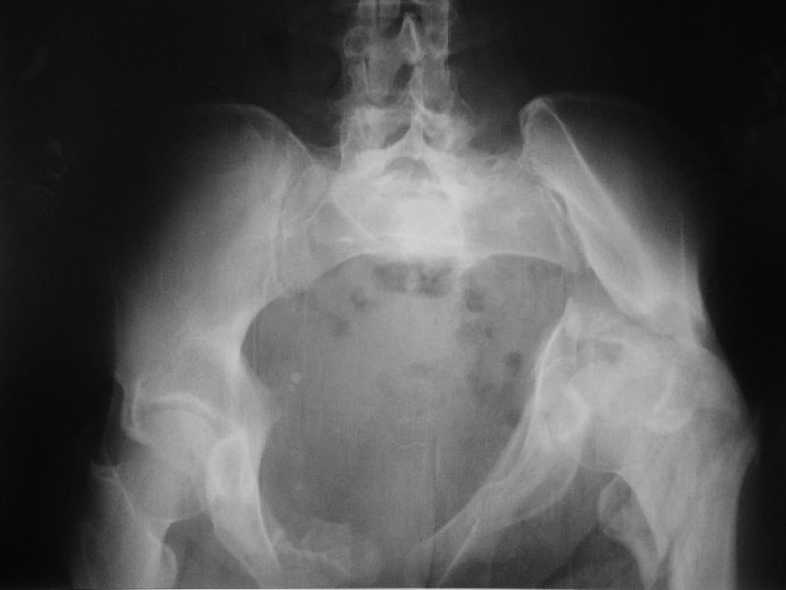

Больная 43 года (промышленный альпинист), 28.07.08 в результате падения с 5 этажа получила политравму: Перелом свода и основания черепа. Вертикально-нестабильное повреждение таза, осложнённое разрывом мочевого пузыря. Чрезвертельный перелом левого бедра. Перелом правой таранной кости, переломовывих правой кубовидной кости. Тупая травма живота, разрыв печени, ушиб почек. Забрюшинная гематома. В день травмы - лапаротомия, ушивание ран печени. Разрыв мочевого пузыря не диагностирован. Течение болезни осложнилось развитием мочевого затёка и обширной пред- и забрюшинной флегмоны, сформировался свищ мочевого пузыря. 19.8.2008 вскрытие, дренировние флегмоны, ревизия мочевого пузыря, обтурация мочевого свища (свищ закрылся в октябре), 1.10.2008 некрэктомия, пластика по Шеде-Лидскому правой кубовидной кости. По результатам КТ диагностирован рак правой почки (диагностическая находка), 8.10.2008 нефрэктомия справа. Переломы велись консервативно. Имеется вертикальное смещение левой половины таза с выраженным отведением крыла (клинически подвижности нет), несросшийся низкий двухколонный перелом левой вертлужной впадины с потерей конгруэнтности, укорочение около5 см, застарелый разрыв лонного сочленения, неправильно сросшиеся переломы обеих ветвей правой лонной кости с укорочением, патологическая подвижность лоно-седалищного фрагмента слева. Правая нижняя конечность неопорна, несмотря на то, что лежа прямую ногу поднимает, ходит на левой ноге (ортопедическая обувь) с костылями, справа тазобедренный ортез. Седалищные нервы работают.Урологи отпустили больную на 6 мес.